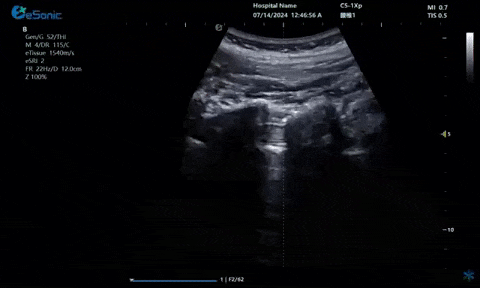

超声引导下蝶颚神经节阻滞术

大雁征-上颌动脉切面